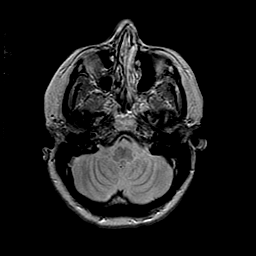

MR Study #2 -- Slice #12